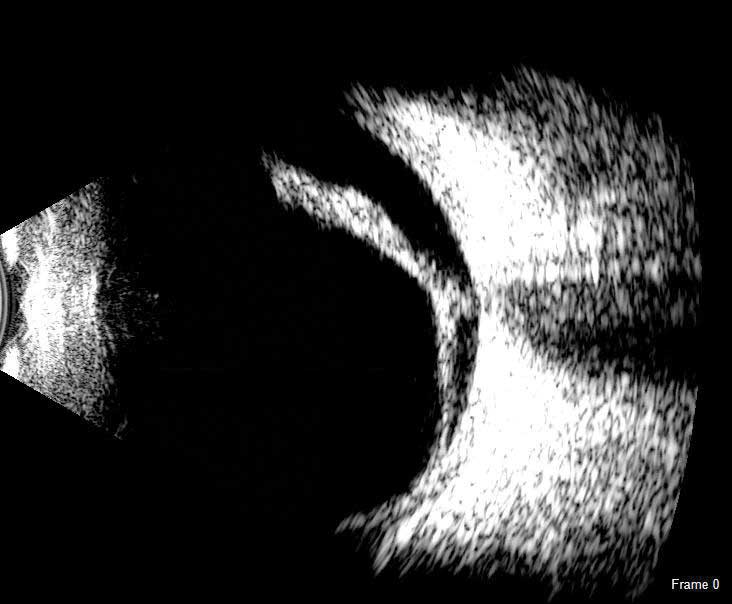

Датчик Scanmate Flex B-Scan дозволяє лікарям отримувати чіткі і точні зображення і відеозаписи заднього відрізка ока. Ультразвукове В-сканування ефективне навіть при наявності помутнінь (таких як щільна катаракта, кров або анатомічні структури), які заважають оптичним технологіям.

Зонд B-Scan доступний з частотами 12,5 МГц і 20 МГц. Серед екранних інструментів є штангенциркуль для вимірювання структур, інструмент для вимірювання площі та інструмент анотації, який дає змогу позначити патології на зображенні.

B-Scan може допомогти в оцінці: Відшарування сітківки або склистого тіла;

Патологій гуморальної оболонки склистого тіла стафіломи, заднього сегмента, судинної оболонки, зорового нерва або потовщення склери.